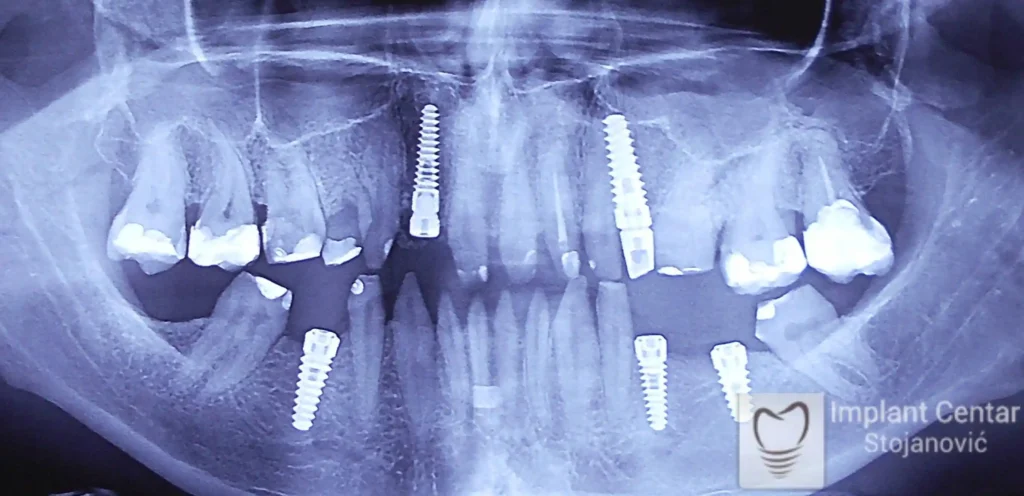

Na slici 1. i slici 2. prikazan je izgled pacijenta pre početka terapije – klinički i rendgenološki.

Nakon vađenja zuba, ugrađeni su implantati. Na slici 3 prikazan je ortopan snimak sa ugrđenim implantatima. Tokom perioda osteointegracije, pacijent je bio zbrinut fiksnim privremenim krunicama na implantatima, koje su izrađene samo dva dana nakon hirurške intervencije.

Na slikama 5. i 6. prikazan je izgled definitivnih cirkonijum-keramičkih mostova na implantatima.